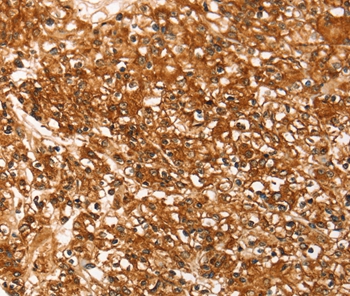

Immunohistochemical analysis of paraffin-embedded Human prostate cancer tissue using #37928 at dilution 1/30.